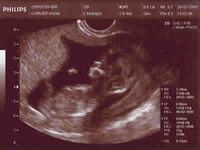

Mes premières photos,

Ma première echographie...